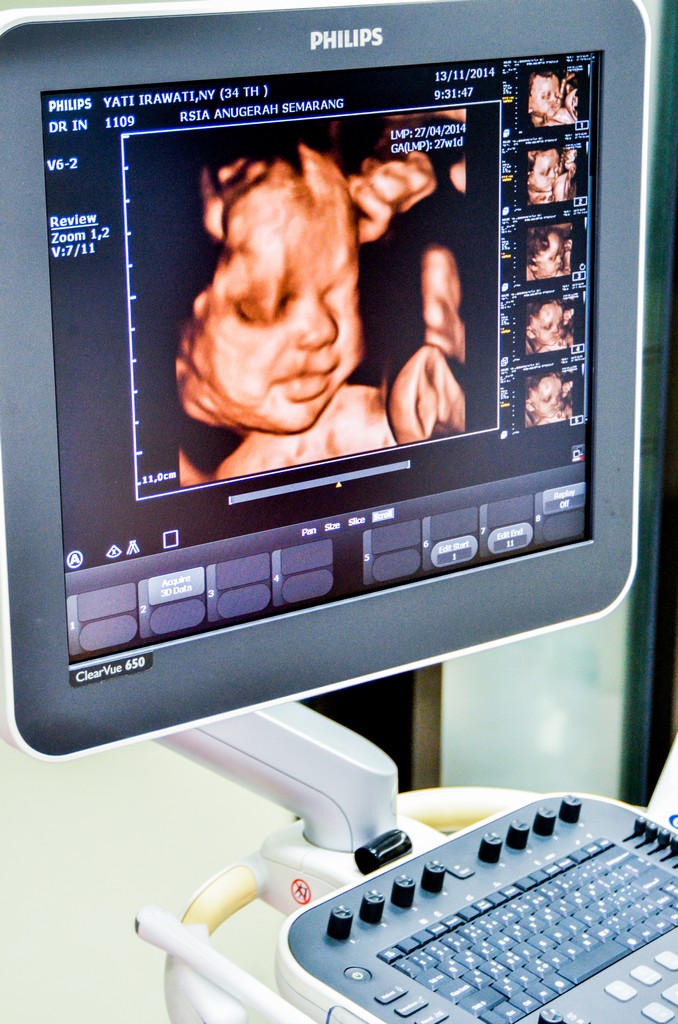

USG 3D/4D dan Pemeriksaan Kelainan Bawaan

Kami dapat menampilkan citraan terbaik dari janin dalam kandungan Anda menggunakan USG 3D / 4D. Kami percaya bahwa sangatlah penting untuk memberikan pemeriksaan yang komprehensif pada kesehatan dan pertumbuhan janin. Berikut adalah beberapa foto dari peralatan dan fasilitas yang kami miliki